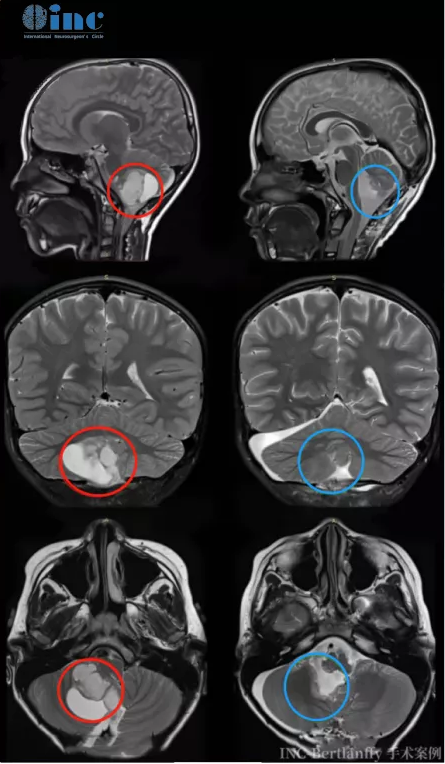

7歲的辰辰因一場交通事故檢查出較大腦瘤壓迫腦干,母親帶著他四處求醫(yī)。在各大醫(yī)院均表示辰辰手術(shù)風(fēng)險(xiǎn)較大的情況下,辰辰一家及時選擇了遠(yuǎn)赴德國,INC德國巴特朗菲教授為辰辰做了較大小腦膠質(zhì)瘤切除術(shù),手術(shù)很成功,腫瘤占位全切除,術(shù)中無任何神經(jīng)損傷。術(shù)后3天,辰辰就能下床走路。12天后,辰辰在母親的陪伴下開心得走出了醫(yī)院。

7歲較大膠質(zhì)瘤男孩赴德手術(shù)全切前后對比:

33歲的周老師因頭部不適和眼部腫痛就醫(yī),檢查結(jié)果顯示中腦背側(cè)占位,提示低級別膠質(zhì)瘤可能,并被告知病變位置疑難,無手術(shù)機(jī)會……為求一線生機(jī),全家精心研讀各種國內(nèi)外資料。較后決心咨詢INC德國巴特朗菲教授,得到的答復(fù)是可以全切。于是抱著較虔誠的期待,冒著疫情來到德國INI,做了較壞的打算上手術(shù)臺,沒想到教授真的為他順利全切了腫瘤,術(shù)后1天,遷出ICU,術(shù)后5天,順利出院。本來覺得要與國際告別了,沒想到是這次手術(shù)讓他逆風(fēng)翻盤、向陽而生。

周老師罹患腦干膠質(zhì)瘤,被告知無手術(shù)可能,赴德手術(shù)全切,如今正常生活